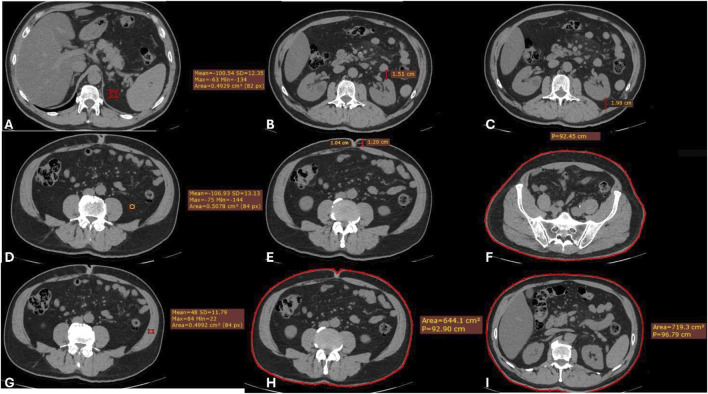

We previously developed and validated LAPDOCTOR (LAParoscopic-Donor-nephreCTomy-scORe), a novel scoring system for the preoperative assessment of the difficulty of living donor nephrectomy (LDN). To prove its significance, we extended our investigation to a prospective, multicenter, national study. Difficulty was assessed by the operating surgeon using a scale from 1 to 3 (1-standard, 2-moderately difficult, 3-very difficult) based on eight parameters: availability of laparoscopic space, mobilization of the colon, kidney, gonadal, adrenal and renal vein, renal artery, and ureter. Donor CT-scans were blindly reviewed by a radiologist, and the LAPDOCTOR scores were compared with the difficulty levels assigned by the surgeon to investigate the match rates. One hundred eighty-five donors were enrolled, with a mean age of 54 years (range 24-77), BMI 25 kg/m2 (range 17-35), and male/female 59/126. LDN was blindly scored as standard in 45% of the cases, moderately-difficult in 52%, and very-difficult in 3%. The agreement between the LAPDOCTOR and expert donor surgeons' rate in categorizing LDN into risk groups had a QWK of 0.711 (95% CI 0.577-0.844) with p < 0.001. The LAPDOCTOR enables precise preoperative determination of the difficulty of LDN, particularly in very difficult cases, and assessment of surgical risk in living kidney donors.

Abstract Image